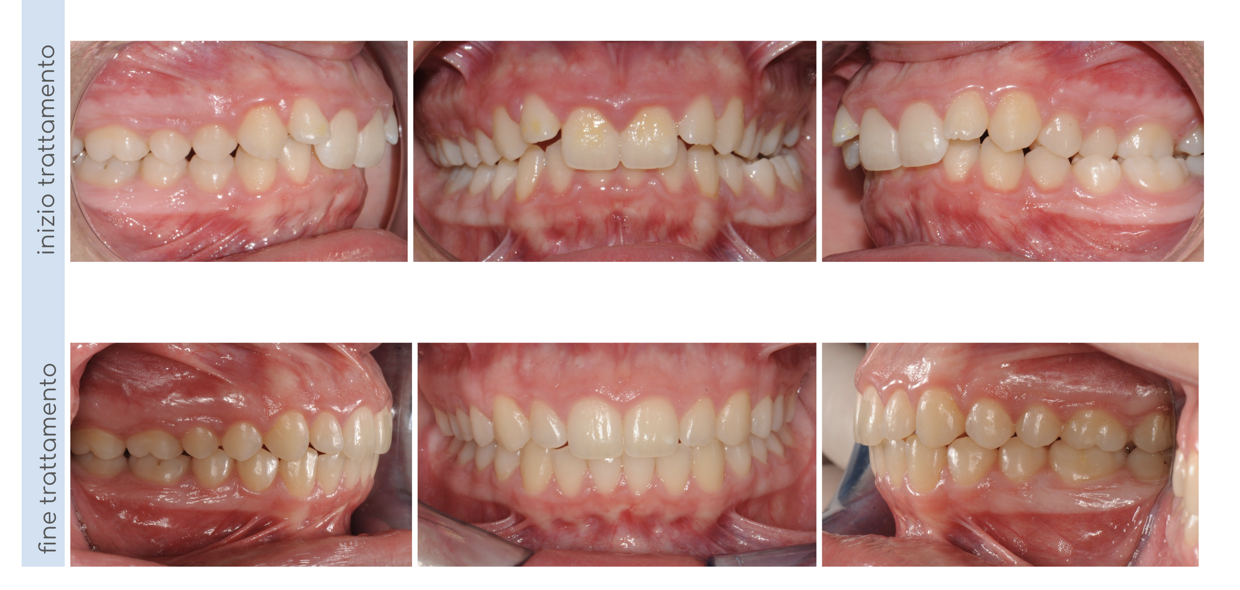

La paziente presentava una Il classe Il divisione con morso profondo, morso crociato posteriore a sinistra e deviazione delle linee mediane dentali. E stata trattata con apparecchio fisso ad entrambe le arcate per 18 mesi; al termine del trattamento abbiamo ottenuto una l classe bilaterale, l'apertura del morso, la correzione del morso crociato posteriore e un allineamento delle linee mediane dentali.